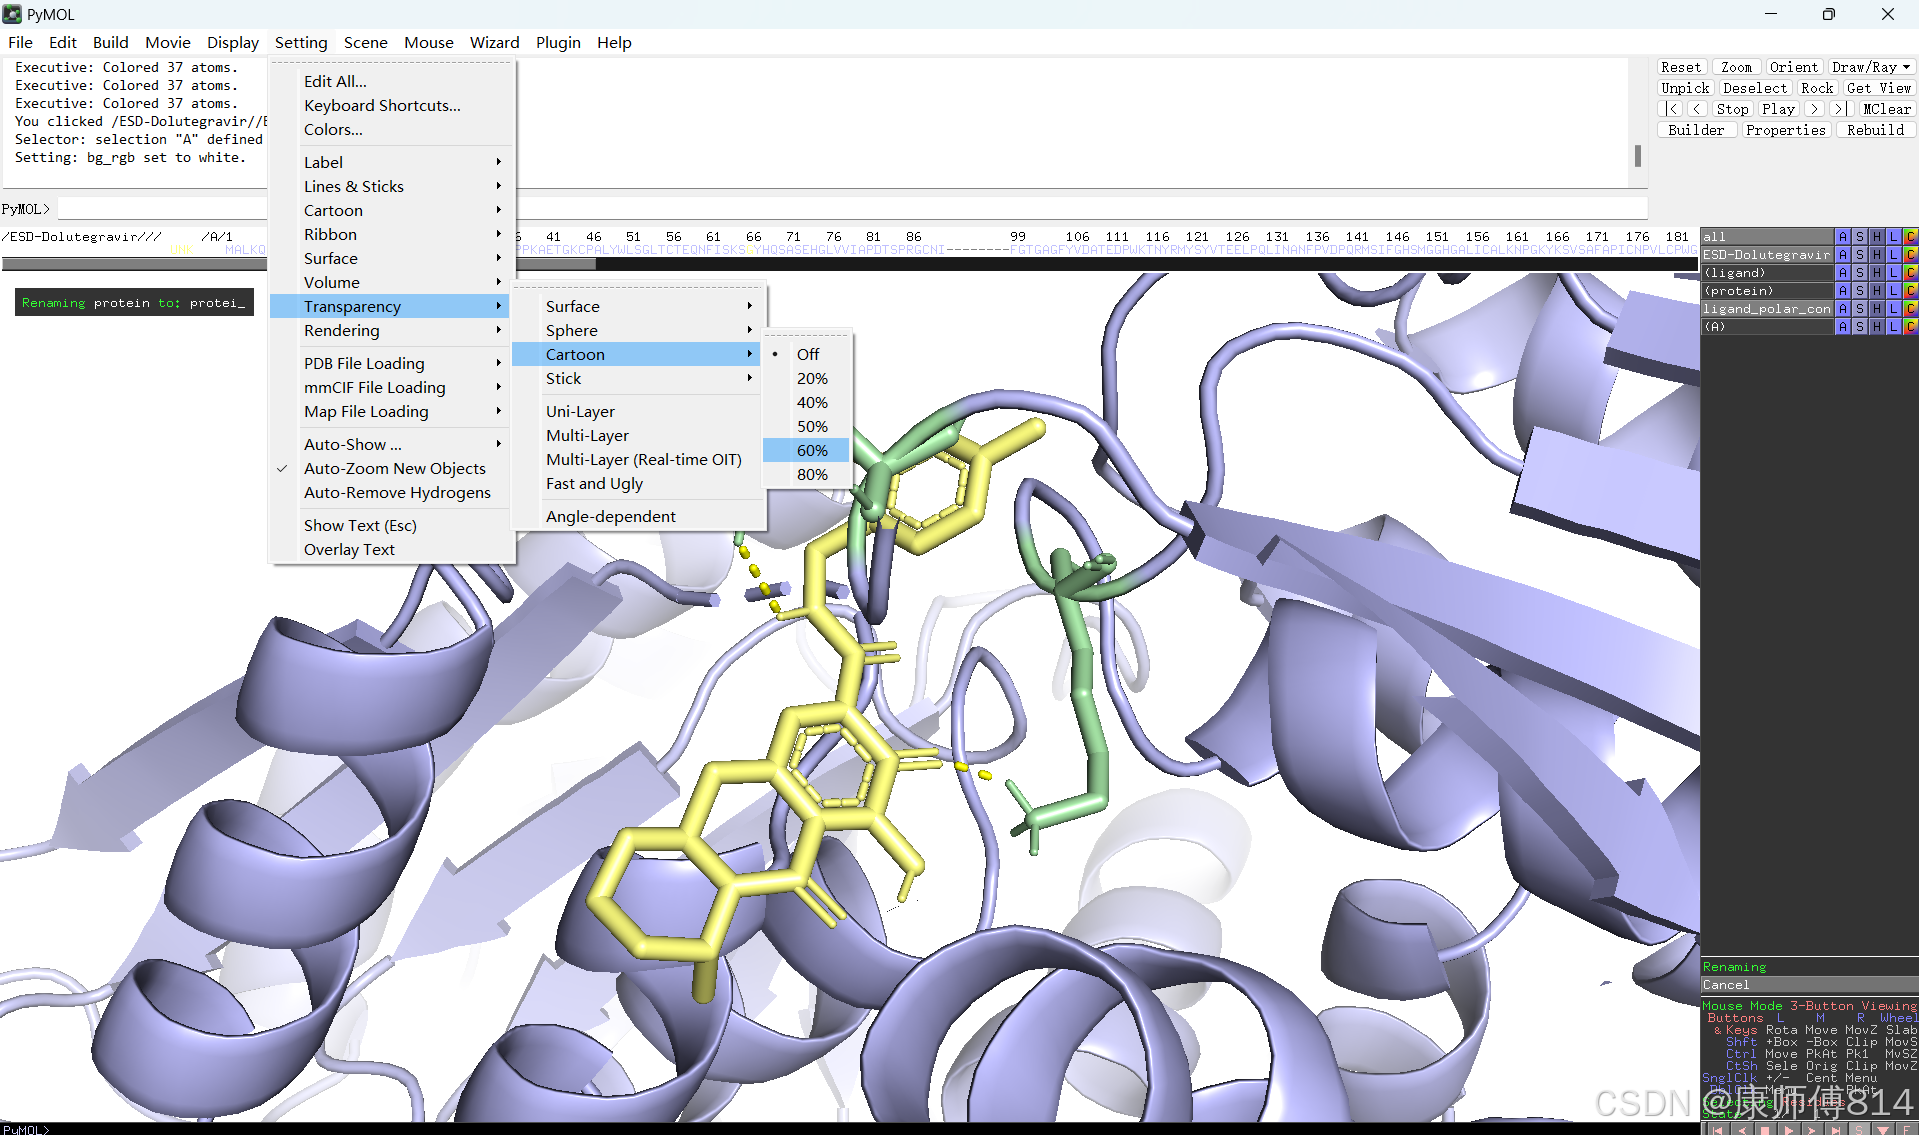

#此时展示分子对接的基本要素已经形成,后续可根据需要修改背景颜色、显示氨基酸残基名字以及氢键键能等等,这里不再赘述

#修改好后就可以导出了,点击右上角Draw,选择合适的格式导出即可

结果演示